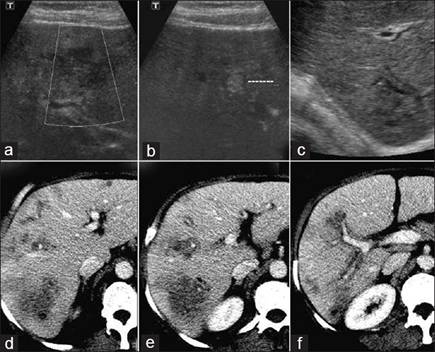

Chẩn đoán huyết thanh học có giá trị vì độ nhạy, đặc hiệu cao cả giai đoạn mạn tính và cấp tính. Đôi khi, sự di chuyển của sán trong túi mật hoặc đường mật được phát hiện qua siêu âm và được xem như là một công cụ chẩn đoán tốt bệnh SLGL và có độ nhạy hơn cả CT scanner trong giai đoạn sán ở đường mật; biểu hiện trên hình ảnh là dày thành ống mật chủ (OMC), hình thể con sán đã chết nằm tại đó hoặc đang chuyển động bên trong OMC hay túi mật. Nhiều nghiên cứu được thực hiện nhằm mô tả đặc điểm tổn thương trên hệ gan mật do sán Fasciola gigantica/ Fasciola hepatica.

Một số thương tổn trên hệ thống gan mật qua khảo sát trên siêu âm trên hơn 1000 ca bệnh tại đa trung tâm, nhiều nhất là tại Phòng khám của Viện Sốt rét-KST-CT Quy Nhơn từ năm 2003 đến nay đã cho thấy hình ảnh thương tổn đa dạng, kích thước khác nhau và tính chất hồi âm khác nhau và có thể tổng hợp dưới đây qua thủ thuật SA bao gồm khảo sát bụng tổng quát, nhu mô gan, túi mật và hệ đường mật. Qua thăm dò, các hình ảnh bất thường liên quan đến nhu mô gan (giai đoạn cấp) là hay gặp nhất, kế đến tổn thương hệ đường mật, túi mật (giai đoạn mạn tính) với nhiều biểu hiện trên hình ảnh đa dạng, trong đó tổn thương tăng âm hình giống chiếc lá hay lưỡi liềm không kèm bóng cản (không có bóng lưng). Tổn thương nhu mô thường là vùng giảm âm phối hợp tăng âm, hoặc cả trống âm với giảm âm và tăng âm (khối hỗn hợp), trông giống như khối di căn, có bờ nham nhở không phân rõ giới hạn, tổn thương nằm cạnh TM cửa cũng chiếm số lượng không nhỏ.

Siêu âm gan mật có thể cho thấy ba loại tổn thương trong giai đoạn cấp tính. Loại tổn thương thứ nhất là hình ảnh nhu mô gan không đồng nhất, đôi khi chỉ một ổ tổn thương, chiếm chủ yếu với 86,32%, kế đến là 2 khối nối liền hoặc nằm riêng lẻ (12,09%) hoặc đa ổ (hiếm gặp hơn) không đáng kể.

Loại tổn thương thứ nhất, tổn thương hầu hết có bờ hoặc viền không rõ ranh giới giữa nhu mô lành và bệnh đi kèm tính chất tăng, giảm, hỗn hợp âm khác nhau: trong đó giảm âm chiếm chủ yếu (83,12%), tiếp đến là hỗn hợp âm (59,86%) và tăng âm (5,25%). Kết quả này cũng phù hợp với một số nghiên cứu trong và ngoài nước (Orhan S và cs., 2004; N.V. Khá và cs., 2006; M.T. Gulssen và cs., 2006; T.V. Lang và cs., 2009; A. Fica và cs., 2012). Bên cạnh các tổn thương như thế chúng tôi còn gặp một tỷ lệ đáng kể là khối echo hỗn hợp tăng âm, giảm âm kèm theo nhiều vùng trống âm (59,86%) tương tự nghiên cứu của Cosme và cộng sự (2003) và N.V.Khá và cộng sự (2006), A. Fica và cộng sự (2012).

Loại tổn thương thứ hai mà chúng tôi hay gặp trong thời gian đầu của cấp tính là các khoảng trống như “khoang” hoặc có nhánh trông giống đường hầm, các dạng tổn thương này nhìn rõ nét hơn nếu so sánh và đối chiếu trên phim chụp CT Scanner hoặc MRI có bơm thuốc cản quang. Đây là những hình ảnh có ngoại vi ngoằn ngoèo, khúc khủy do quá trình sán di chuyển trong nhu mô gan và trong y văn ký sinh trùng cũng từng đề cập (F.Mansour Ghanaei và cs., 2006).

Trong giai đoạn này, hình ảnh trên SA điển hình thường là đa ổ nhỏ, li ti có thể vừa gặp trong nhu mô gan vừa gặp trong đường mật (3,13%), bao gồm OMC; nhưng phần lớn là hình ảnh thả nổi (floating) hoặc vết (trace) tăng âm di động bên trong túi mật hoặc OMC mà không kèm bóng cản với tỷ lệ 1,84%, có thể là sán di chuyển hoặc xác sán chết dính lại. Một dấu hiệu nữa không đặc trưng cho giai đoạn mạn tính là hình ảnh dãn, phù nề và dày thành túi mật (2,52%), đường mật (2,85%) không đều các đoạn, các dầu hiệu này cũng thường gặp trong bệnh cảnh viêm xơ đường mật hoặc viêm đường mật lan tỏa trên cơ địa suy giảm miễn dịch HIV/AIDS (Mansoeu Ghanael và cs., 2006). Kết quả ở đây tương tự như nhận định của nhiều tác giả báo cáo trên thế giới, đặc biệt các nghiên cứu tại Cuba cũng cho một số hình ảnh tương tự: những vệt thẳng tăng âm trong túi mật, dãn đường mật và nhất là dãn OMC đi kèm với vệt tăng âm bên trong lòng OMC hoặc túi mật (Orhan S và cs., 2004; Gulssen và cs., 2006; A. Fica và cs., 2012).

Nghiên cứu khảo sát đã phát hiện các vùng tăng âm nhỏ không có bóng lưng kèm với dãn đường mật có thể sán đang ở trong, điểm này có thể phân biệt được với sỏi hoặc vật thể khác của đường mật (có bóng lưng). Lẽ đương nhiên, một số ca sán dính chặt vào thành túi mật, khi đó việc phân biệt sán hay polyp dạng tuyến (adenomatous polyps) thì rất khó vì đều có tính chất tăng âm và không bóng lưng. Nếu một vài con sán di động thì quá dễ dàng để phân biệt các tình huống trên.

Vấn đề nữa đặt ra là khi có ảnh hưởng đồng thời cả gan và mật thì chúng ta cần lưu ý một số hình ảnh trên siêu âm trông giống ổ tăng âm không kèm bóng lưng trong túi mật hoặc đường mật đi với hình vết, chiếc lá hoặc hình liềm thì có lợi cho chẩn đoán, nhất là trong vùng lưu hành bệnh như miền Trung-Tây Nguyên hay khu vực Altiplano Nam Mỹ thì chẩn đoán xác định SLGL hoặc nghĩ đến SLGL là ấn tượng đầu tiên. Nếu là các liên quan tổn thương nhu mô các phân thùy gan (P) và quanh tính mạch cửa thì cần chú ý đến, song cũng không nên vì thế mà bỏ qua các chẩn đoán có thể khác.Nhìn chung, siêu âm có thể cho thấy hình ảnh tổn thương giảm âm (hypodense/hypoechoic lesions) trong gan phù hợp với đường đào hầm đi của ấu trùng. SA có thể phát hiện sán trưởng thành trong đường mật hoặc túi mật. SA hiếm khi nhìn thấy tình trạng bụng báng và tràn dịch do sán.

CT scanner có thể cho thấy hình ảnh đa khối tổn thương có kích thước 1-10 mm hoặc các đường hầm trong nhu mô gan-một mô hình lan rộng từ các đường hầm. CT scanner cũng có thể thấy sán trưởng thành trong đường mật hoặc túi mật. Các khảo sát bằng siêu âm và CT scanner đôi khi cũng nhầm lẫn với sỏi và khối thương tổn ác tính. Việc khảo sát cho nhiều lát cắt khác nhau và kích thước và độ dày mỏng khác nhau